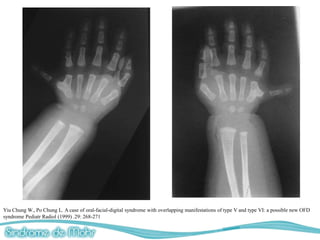

Alteraciones digitales

• Polidactilia postaxial/preaxial en manos y pies

(Hexadactilia)

• Sindactilia

• Braquidactilia

• Polosindactilia de los dedos gordos del pie.

– Radiografias (manos, pies, cabeza)

Naohiko Sakai, et al. Oral-Facial-Digital Syndrome Type II (Mohr Syndrome): Clinical and genetic manifestations

Yiu Chung W., Po Chung L. A case of oral-facial-digital syndrome with overlapping manifestations of type V and type VI: a possible new OFD

syndrome Pediatr Radiol (1999) .29: 268-271